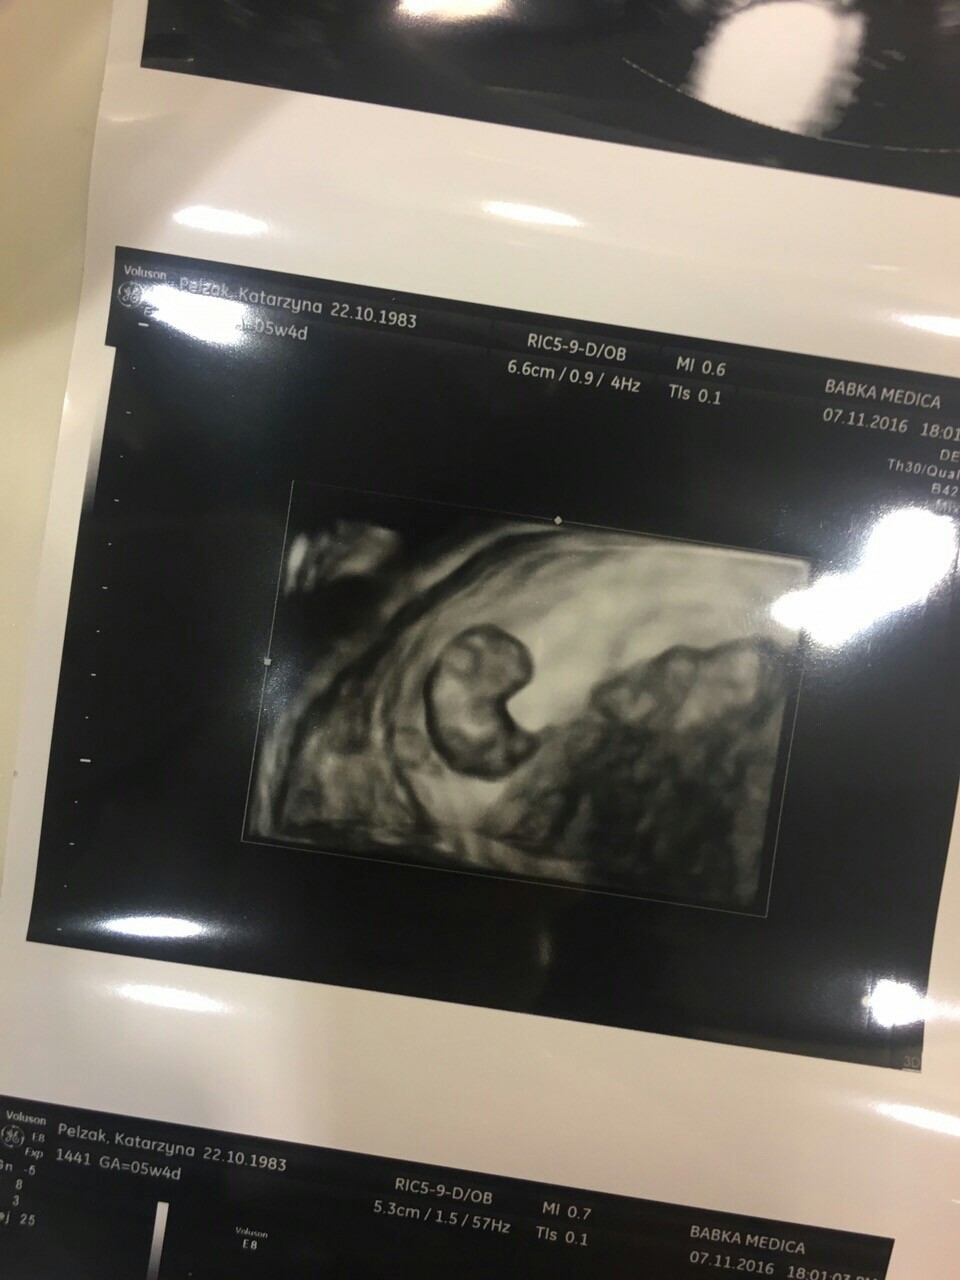

Czy można dołączyć? Wyglada na to, ze mam najstarsza ciaze, jakos szybko miałam owu i to moj 8-9 tydzień choć wg OM dopiero 7.

Byłam juz na USG dziec ma sie super, serduszko ładnie bije. To moja 3cia ciąża. Mam w domu Grzesia 4,5 roku i Michasia 2 latka

W załączniku maluszek